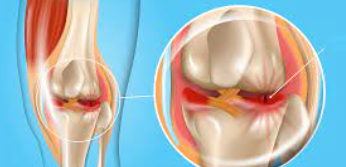

무릎 연골 손상의 가장 대표적인 증상은 무릎 관절 부위의 통증입니다. 초기에는 운동 후나 장시간 활동 후에만 나타나지만, 손상이 진행되면서 일상적인 움직임에서도 통증이 발생합니다. 특히 계단을 오르내리거나 쪼그려 앉는 동작에서 통증이 심화되는 특징을 보입니다.

연골 손상으로 인한 통증은 날카로운 찌르는 듯한 통증보다는 둔하고 깊은 곳에서 느껴지는 통증의 양상을 보입니다. 무릎을 직접 눌렀을 때 압통이 느껴지며, 특히 무릎뼈 주변과 관절선 부위에서 압통이 두드러집니다.

무릎 부종과 열감

연골 손상이 발생하면 관절 내 염증 반응으로 인해 무릎 관절에 부종이 나타납니다. 부종은 무릎 전체가 붓는 양상을 보이며, 손으로 만져보면 열감이 느껴지기도 합니다. 부종으로 인해 무릎의 모양이 변형되어 보이며, 무릎을 완전히 구부리거나 펴는 것이 어려워집니다.

아침에 일어났을 때 부종이 더 심하게 나타나는 경우가 많으며, 활동을 시작하면서 점차 완화되는 특징을 보입니다. 하지만 과도한 활동 후에는 다시 부종이 악화되는 양상을 보입니다.

관절 소리와 마찰감

무릎 연골 손상 시 특징적으로 나타나는 증상 중 하나는 관절에서 나는 소리입니다. 무릎을 구부리거나 펼 때 '딱딱', '삐걱' 하는 소리가 나며, 이를 의학적으로 '관절음'이라고 합니다. 이는 손상된 연골 표면이 거칠어져서 뼈와 뼈 사이의 마찰이 증가하기 때문입니다.

손으로 무릎을 만지면서 관절을 움직여보면 뼈끼리 문지르는 듯한 마찰감을 느낄 수 있습니다. 이러한 마찰감은 연골 손상의 정도가 심할수록 더욱 뚜렷하게 나타납니다.